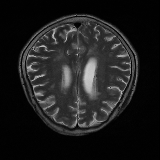

The Flair experiment results are obtained using a training of two cycles in the first stage and four cycles in the second stage to reach the peak separation, and the threshold value is taken at the intensity of 170. For T2 we use two cycles in the first stage and two cycles in the second stage, and the threshold is taken at 220. Both thresholds are taken based on the rightmost peaks of the histograms of reconstructed images. We obtain a subject-wise mean dice score of 79.89% on the Flair scans and 88.57% on the T2 scans. Despite the lower score compared to T2, the Flair modality provides the potential of identifying additional anomalies, which may not be limited to HGG or LGG, as shown in the third column of Fig. 6. However, since the focus of this experiment is to segment HGG and LGG only, using the T2 modality outperforms the Flair in term of the Dice scores as reported in Table 2, and the predicted masks as shown in Fig. 6. Aside from that, on the Flair scans our method suffers both under- and over-segmentation as shown in Fig. 7 and struggles to segment tumors using one uniform threshold as shown in Fig. 8. Typically, we use the rightmost peak as the threshold for brighter tumors; however, the peaks separating tumors in these cases of Fig. 8 occur as the leftmost peak. Such flip further lowers the segmentation score, even though the algorithm is able to separate the anomaly as one of the two cuts.

Although our method has consistently better performance of segmenting brain tumors on T2, as shown from Fig. 6 to Fig. 8. In the case of T2, the primary disadvantages occur due to the inclusion of other regions, such as Cerebrospinal Fluid (CSF), eyeballs, etc., which appear dark in the Flair modality. In order to alleviate these false positives on T2 scans, we multiply the predicted masks with the Flair input images. Then we re-calibrate the output by taking a threshold at the intensity of 50 (roughly 0.2 in the range [0,1]) to generate our final mask. This post-processing is our new choice for the private dataset. We did not use the erosion/dilation operation because it is more efficient for cases with discontinuous segmentation results, which is the one our public datasets suffer with, as shown in Fig. 4, but not our private dataset. This new post-processing improves the performance to a patient-wise mean dice score of 91.58% on T2 scans with two-fold cross validation.